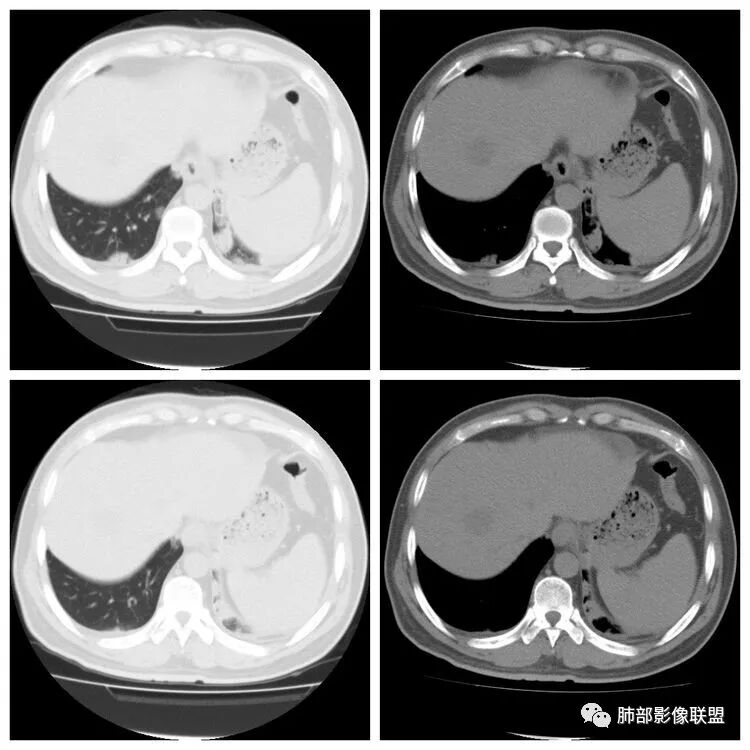

腹增强CT

若尘:腹部动脉增强不像脓肿没意见:肝功异常了,小心张立:增强后表现很明显,很好区别。初学者:我说实话那个腹部给的增强图片对比度调的不好不太像囊肿低密度和边缘不是非常清楚。但是图片给的不好,不是非常能肯定。wonderful:增强的话 脓肿壁会强化 这是鉴别点?初学者:对,但是有时候不会典型

脾大,肝内结节中央似有点状血管通过,炎性可能

但不是典型的脓肿南边:综合临床,影像,肺部是血道来源感染,肺克雷伯杆菌肺炎放前面。毛霉菌待排吧没意见:低蛋白、ALT异常可能间接提示肝脏问题go and see:这个肝脓肿确实不够典型多少。初学者:

4.本例肝脏的病灶并未出现典型肝脓肿图像特征,病灶密度及中央血管样结构显然不符合一般的囊肿。应当说,它是感染灶,但并未液化形成脓腔。